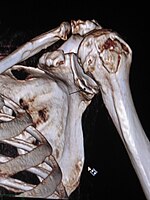

Bankart's fracture Arthur Bankart Fracture of anterior glenoid associated with anterior shoulder dislocation External rotation and abduction of shoulder [2][3] 3-D CT reconstruction of Bankart lesion which occurred post anterior shoulder dislocation.jpg